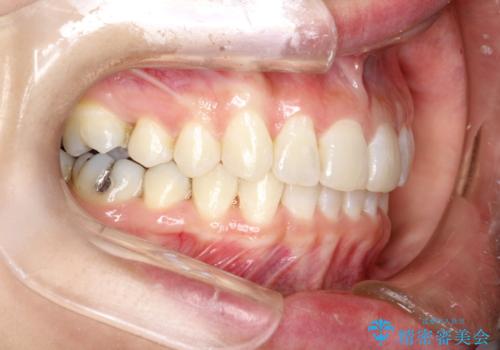

- 前歯のがたつきを気にされて来院されました。

右上の前から2番目の歯が前方に大きく傾いており、下の前歯もガタガタしていました。

インビザラインにて、歯と歯のあいだをわずかに削り並べる計画としました。

しっかりとマウスピースを使用していただけたので、順調に治療を終えることができました